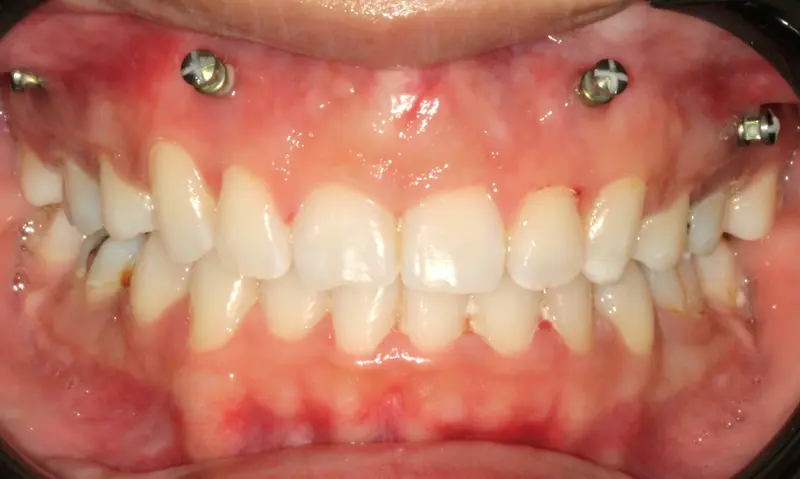

The Diagnosis

Deep bite with over-erupted upper central incisors. The patient presented with a "Gummy Smile" and uneven gingival margins, where the front teeth sat too low relative to the upper lip.

The Engineering

We utilized Temporary Anchorage Devices (TADs) to apply pure intrusive forces. By anchoring to the bone, we lifted the anterior teeth and gum line upwards (Intrusion) to reduce the gummy display and level the smile arc without jaw surgery.

Instrument: Intelligent Brackets + TADs

After treatment: Vertical Control & Intrusion

After

Before treatment: Vertical Control & Intrusion

Before